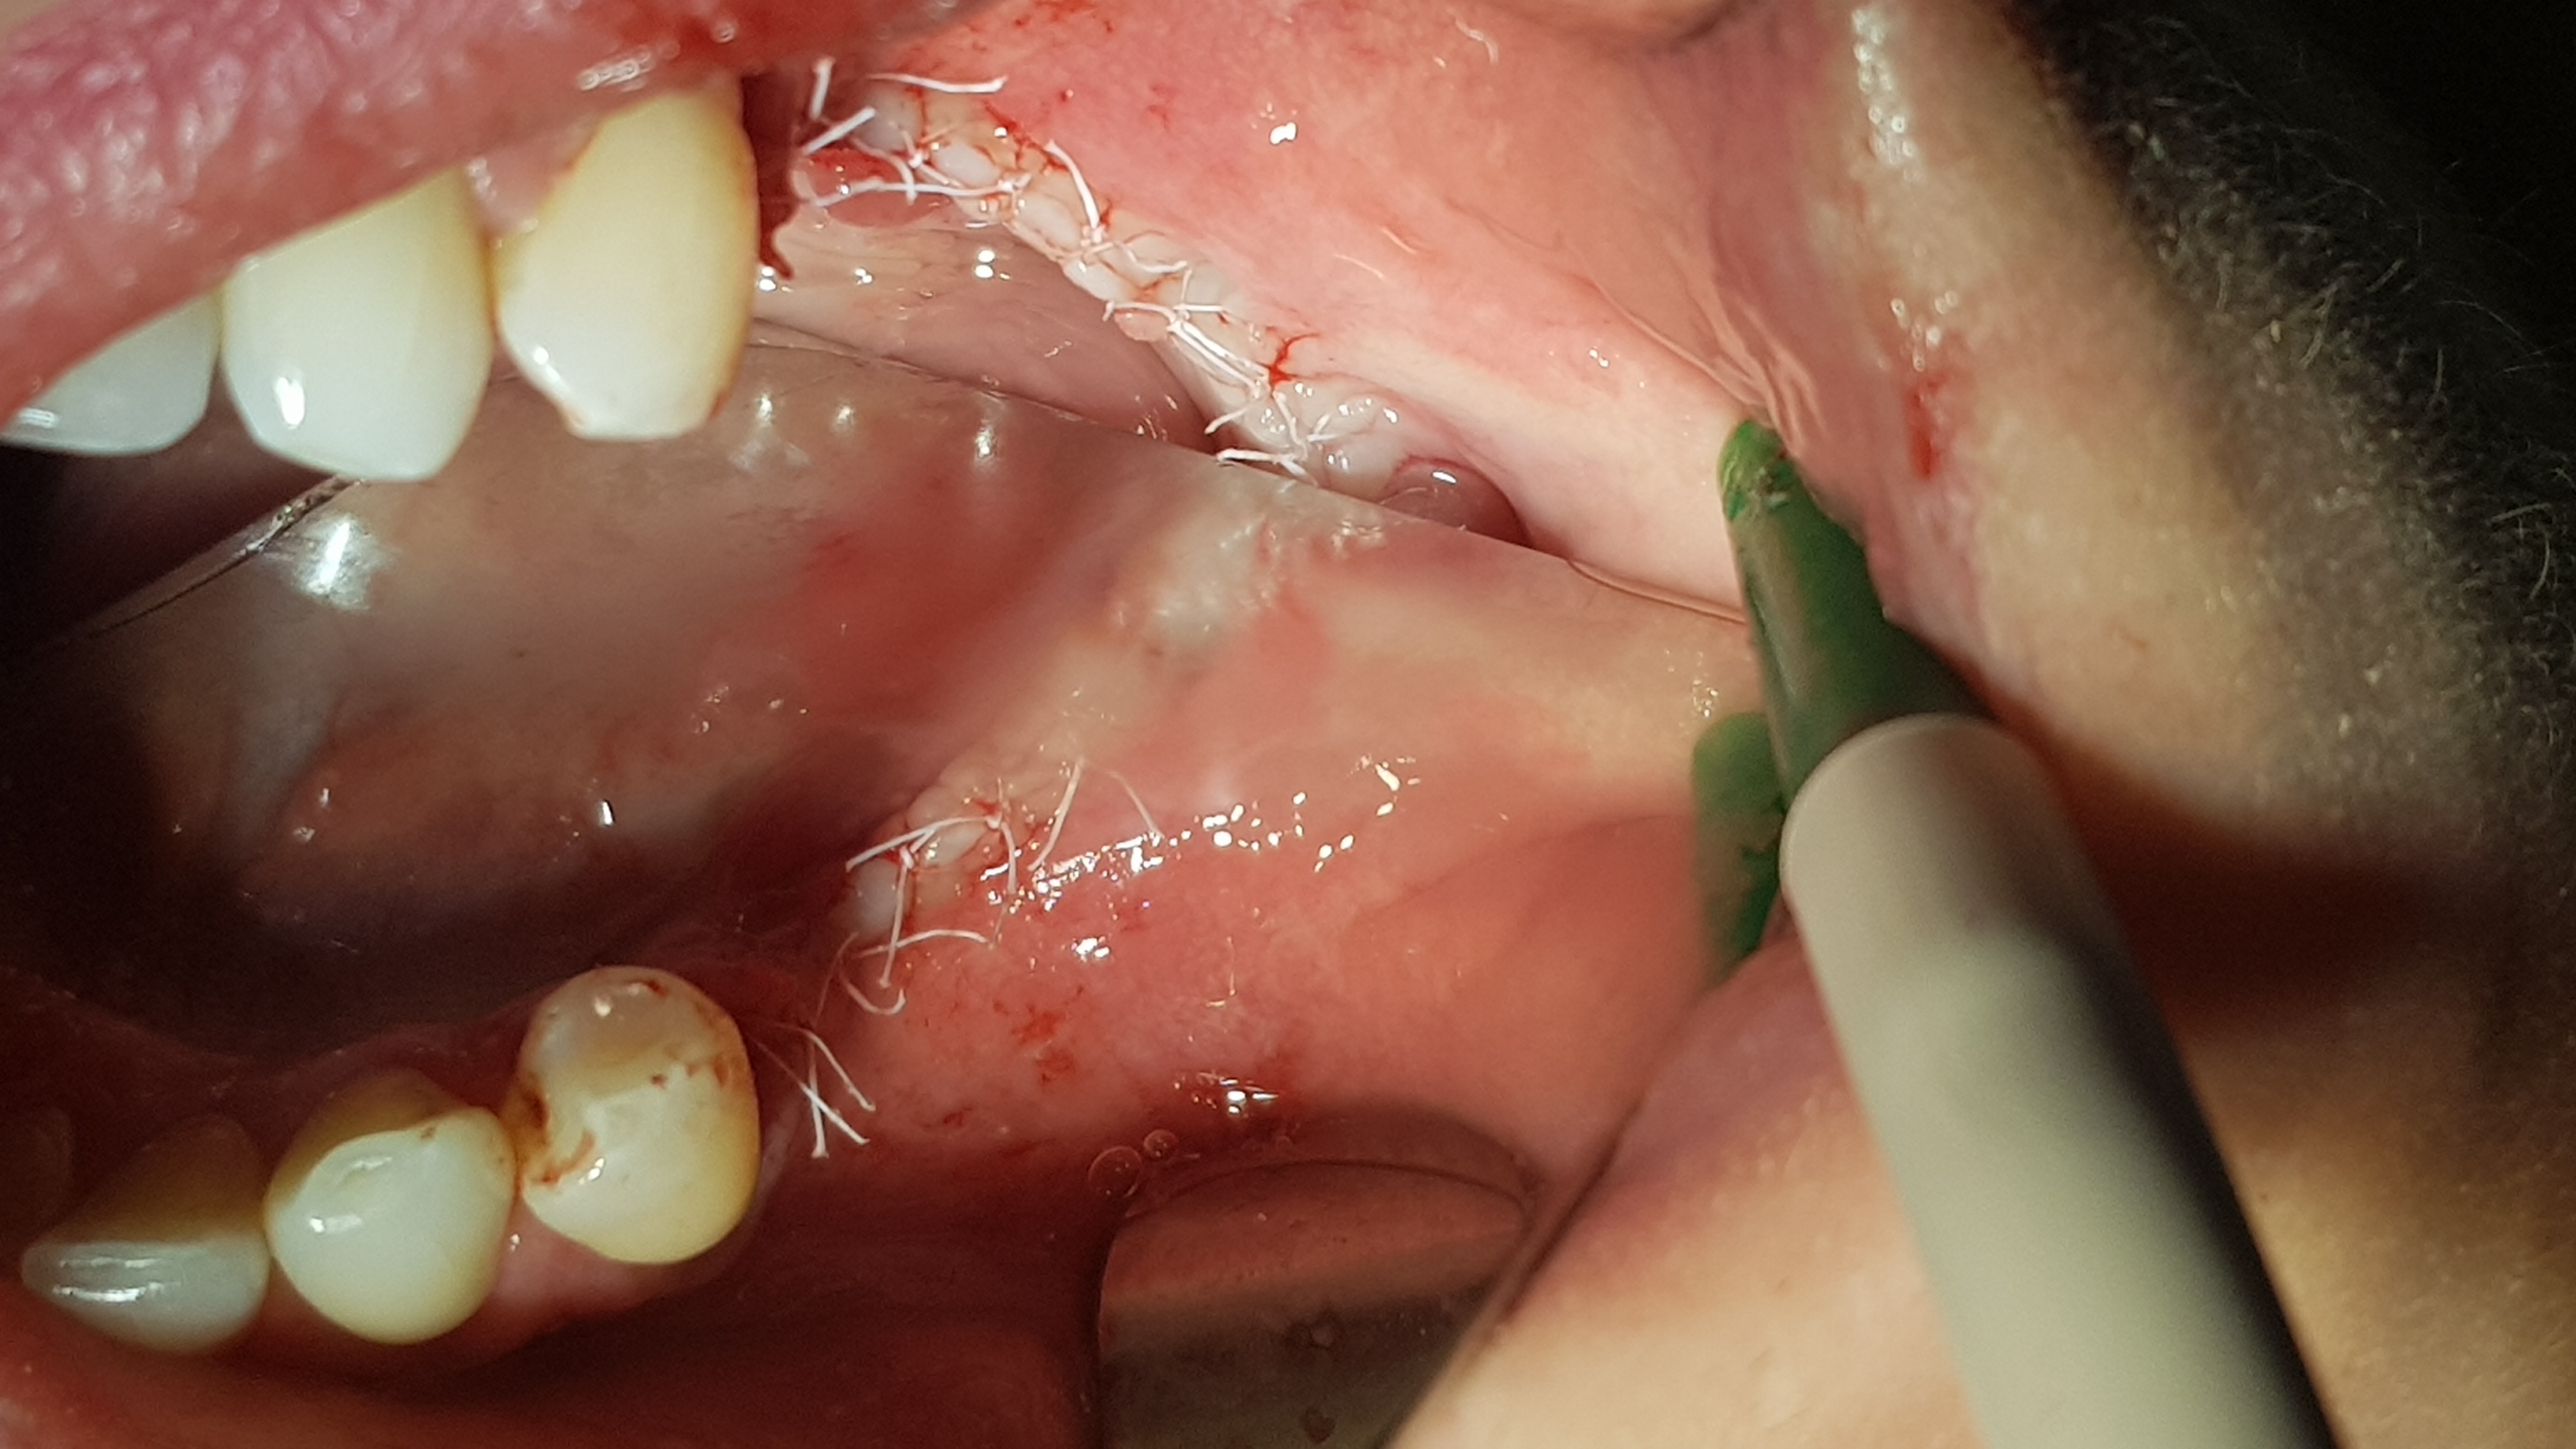

Implanty odsłonięto po kolejnych 3 miesiącach (ryc. 21) i zaopatrzono śrubami gojącymi (ryc. 22, 23).

Ryc. 21. Odsłonięcie implantów po 3 miesiącach.

Ryc. 22. Kontrola rtg prawidłowego umocowania śrub gojących.

Ryc. 23. Kontrola rtg umiejscowienia transferów wyciskowych.

Następnie wykonano suprastrukturę protetyczną (most pełnoceramiczny) cementowaną (ryc. 24).

Ryc. 24. Łączniki protetyczne